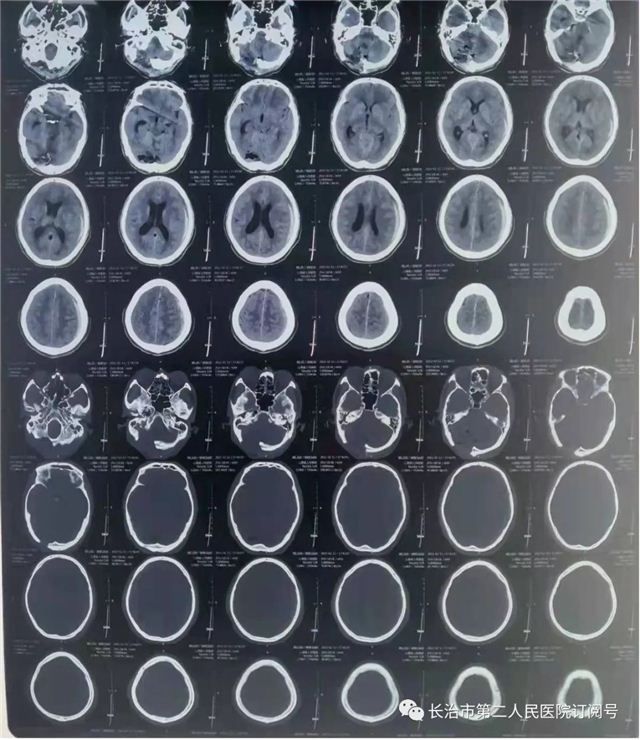

▲术后复查肿瘤全切,术野干净

▲术后复查:肿瘤全切、术野干净未见出血